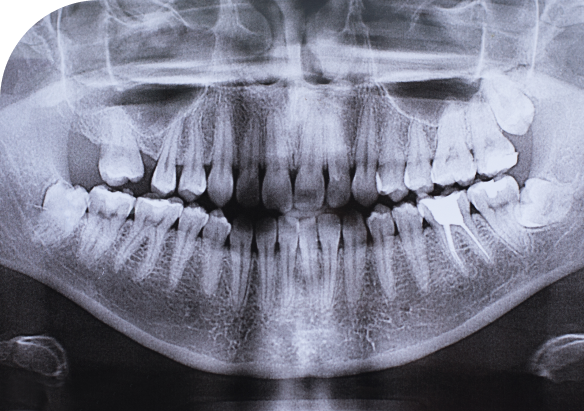

- Детская стоматология – определения положения зачатков постоянных зубов.

- увидеть зачатки постоянных зубов у детей;

- определить строки смены молочных зубов на постоянные;